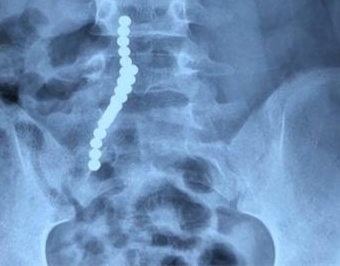

现在孩子的玩具种类非常多,一些玩具还会标注所谓的益智类开发孩子大脑等等,为了能让孩子开心,父母一般都会满足孩子的需求。然后,一些玩具背后就存在着很大的安全隐患。今天我们就来说说,一位九岁的少女因为误吞了磁力珠,险些丧命。